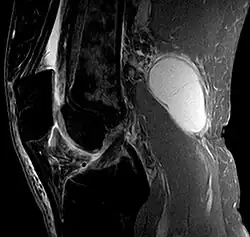

Risk factors include other knee problems such as osteoarthritis, meniscal tears, or rheumatoid arthritis.[1][3][4] The underlying mechanism involves the flow of synovial fluid from the knee joint to the gastrocnemio-semimembranosus bursa, resulting in its expansion.[1] The diagnosis may be confirmed with ultrasound or magnetic resonance imaging (MRI).[3]

Diagnosis is by examination. A Baker's cyst is easier to see from behind with the patient standing with knees fully extended. It is most easily palpated (felt) with the knee partially flexed. Diagnosis is confirmed by ultrasonography, although if needed and there is no suspicion of a popliteal artery aneurysm then aspiration of synovial fluid from the cyst may be undertaken with care. An MRI image can reveal presence of a Baker's cyst.